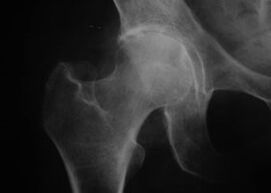

Tagraíonn arthrosis do phróisis degenerative-athlastacha agus forbraíonn sé mar gheall ar athruithe a bhaineann le haois i struchtúr fíocháin cartilage.

Is é príomhchúis na n-athruithe paiteolaíocha ná neamhoird meitibileach sa cartilage. Mar thoradh ar shárú trófachta cartilage caillteanas do-aisiompaithe de proteoglycans agus caillteanas leaisteachas fíocháin.

Is éard atá i gceist le hathruithe dystrophic i cartilage athruithe paiteolaíocha i struchtúr dromchlaí articular cnámha. Le himeacht ama, leathnaíonn an próiseas díghiniúna chuig na fíocháin periarticular.

Ag an gcéad chéim, tarlaíonn athruithe sa sreabhach comhpháirteach. Cuirtear isteach ar chothú an cartilage, agus laghdaítear a fhriotaíocht ar strus. Is cosúil go garbh ar dhromchla an cartilage, agus forbraíonn athlasadh, ag gabháil le pian.

De réir mar a théann an galar ar aghaidh go dtí an dara céim, déantar gnáthchónaí ar an bpian, agus éiríonn cúrsa an athlasadh a théann leis mar thonnta. Tosaíonn an cartilage ag dul in olcas, agus foirmíonn fás cnámh cúitimh ag imill an limistéir articular. Tá baint ag matáin periarticular le próisis paiteolaíocha.

Tá an tríú céim tréithrithe ag ídiú mór cartilage articular le réimsí scrios fíocháin iomlán. Bíonn athruithe anatamaíocha do-aisiompaithe mar thoradh ar phróisis degenerative, lena n-áirítear athruithe ar ais na géaga. Cuirtear isteach ar fheidhm an ghaireas ligamentous, feictear soghluaisteacht neamhghnácha sa chomhpháirteach difear i gcoinne chúlra na soghluaisteachta nádúrtha teoranta.